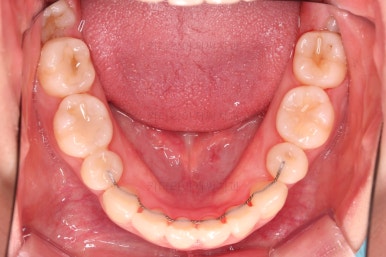

마찬가지로 초진 시 입안의 모습인데요.

전반적으로 약간 삐뚤지만 특히 윗니 앞니가 삐뚤고요.

송곳니는 덧니처럼 튀어나와 보이네요.

그리고 전반적으로 치아가 앞쪽으로 경사되어 있어서 앞니는 뻗친 느낌이 있네요.

가지런하게 하면서 앞니를 뒤로 당겨줘야 여러 가지 문제점들이 개선되기 때문에 발치교정을 했어요.